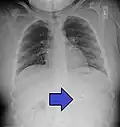

A coin seen on AP CXR in the esophagus -

A coin seen on lateral CXR in the esophagus -